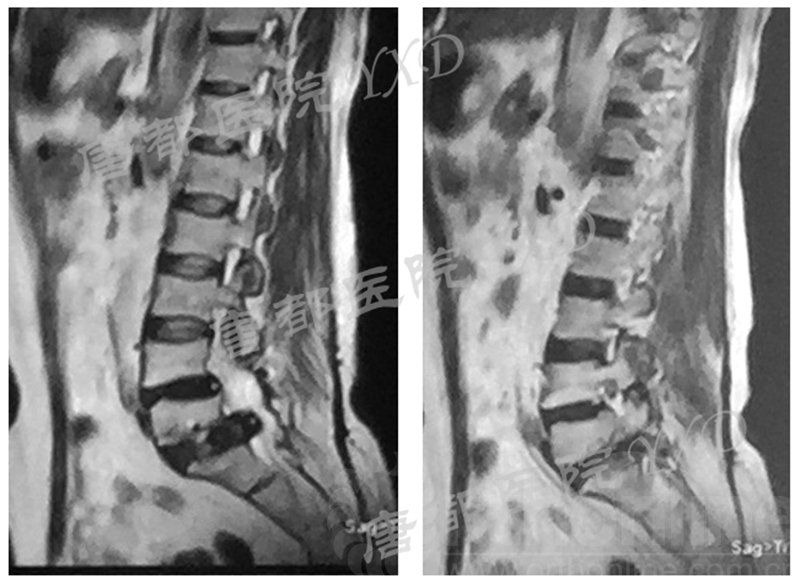

影像学检查:

诊断:腰椎椎间融合术后融合器后移

手术方案:显微镜辅助MI-TLIF腰椎翻修术

术中视频:http://api.orthonline.com.cn/attach/Case3.mp4(术中发现因前次手术全椎板及关节突切除,TLIF的第一步,即关节突关节的定位落脚点难以找到。显微镜下通过Kambin三角解剖位置,进行从外至内的解剖,寻找cage尾端;此外,因大量瘢痕渗血,难以进行充分止血;但在显微镜的照明和放大视野下,操作均可在不伤及神经的前提下进行。由于终板骨质吸收,椎间隙塌陷,导致术野内可同时看到出行根和走行根。而在显微镜下,能够通过调整景深和视线角度,精准充分处理椎间隙骨性终板。无手术并发症)